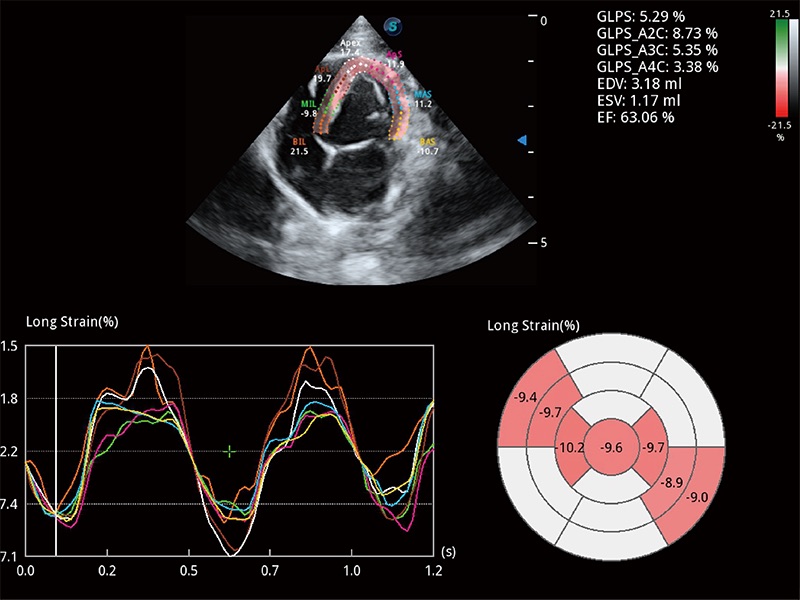

通過心肌識別技術(shù)與二維斑點追蹤技術(shù)相結(jié)合,對心臟的超聲圖像進(jìn)行量化分析。計算心肌17個節(jié)段的應(yīng)變、應(yīng)變率、速度、位移等,并通過牛眼圖的形式進(jìn)行呈現(xiàn)。

能夠基于左心室壁追蹤和辛普森法,自動計算射血分?jǐn)?shù),支持多個可移動點描跡,與手動測量相比,極大節(jié)省了動物醫(yī)生的時間和精力。